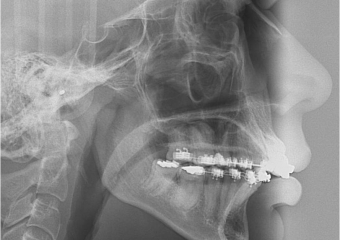

Telerradiografia final